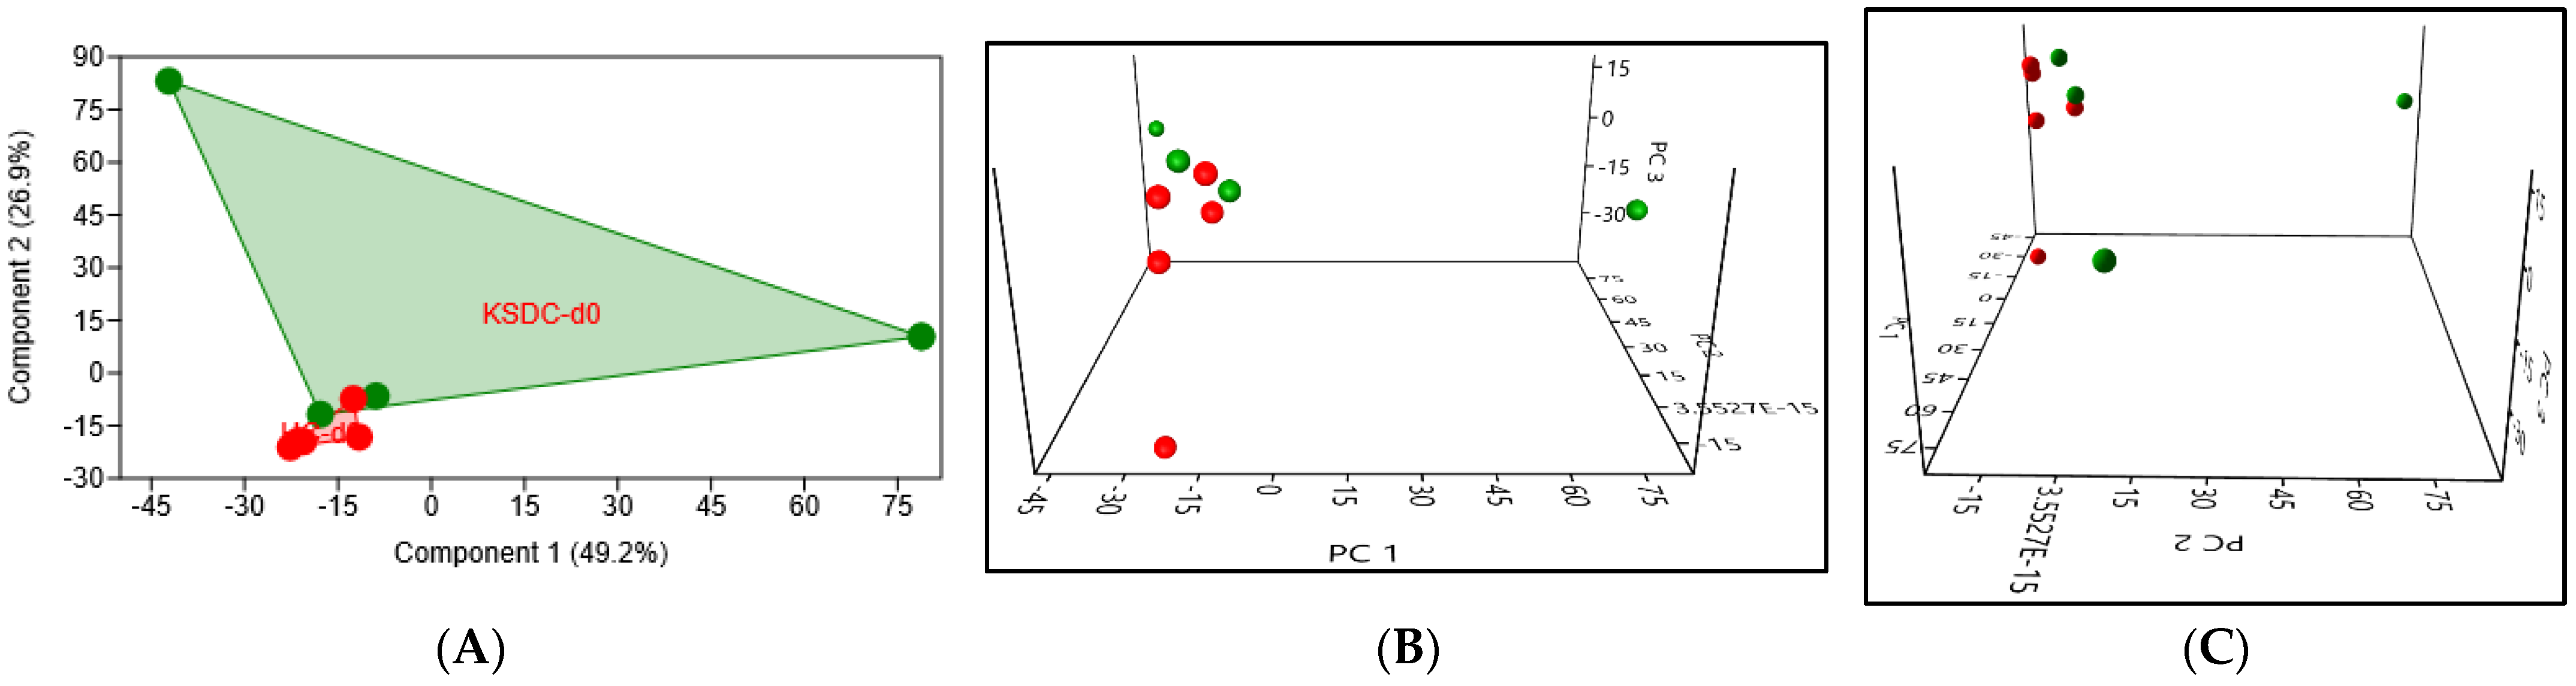

3.2.2. Beta Diversity

Taxonomic Analysis of the Intestinal Microbiota Composition at D0 in the Two Cat Populations

Biodiversity of the Fecal Microbiota in the Two Cat Populations

4.1.3. Beta Diversity